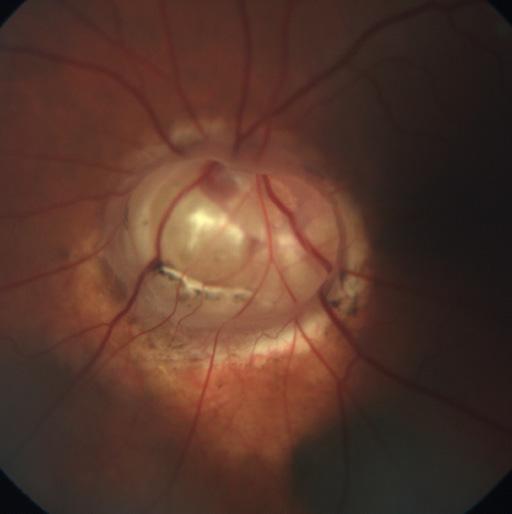

Case 1

Severe lens subluxation in the right eye of a 5-year-old MN mix breed dog. The pupil had been accidentally pharmacologically dilated.

The cornea shows a central focal area of mild edema, cause unknown (Figure 1). Uncharacteristically for cases of primary lens luxation, the lens has not been displaced by gravity (in the anterior chamber or posterior segment), but is still partially connected to the dorsotemporal zonular ligaments.

A focal posterior synechia is also visible, furtherly anchoring the lens to the iris. The lens itself, as it is expected in chronic lens luxation cases, is starting to show the presence of cataracts, equatorial and diffuse cortical. The large aphakic crescent visible on the right of the lens shows an out-of-focus fundus, with a prominent pinkish optic nerve head and dorsal green-yellow tapetum.

The owner of the pet elected conservative miotic treatment and the dog was lost to follow up.

NIKON D70, f/14, 1/60’’, focal length 105 mm, 3.8 max aperture, auto flash.

Case 3

Traumatic cataract in the right eye of a 3-year-old FS Siberian Husky mix breed dog.

The pet was adopted by the owners a few weeks prior to presentation. She had a history of injuries on both eyes, cause unknown, and was almost completely blind. The left eye showed such severe end-stage lesions that enucleation was recommended.

The right eye, which is represented in Figures 3 and 4, was still partially visual.

The eye shows minor conjunctival hyperemia. The pupil is pharmacologically dilated. The lens presents immature diffuse anterior and posterior cortical cataracts. A solid, roughly round dark foreign body is visible in a dorsal/central position within the lens (Figure 3). A radiograph of the dog’s head revealed multiple lesions from penetrated shotgun pellets. It was assumed that the small round foreign body within the right lens was indeed a birdshot and the cause of the cataract. Due to the absence of corneal scars, it was assumed that the pellet had penetrated the lens from the side and the back, perforating the sclera. The left eye had suffered much more severe injuries, and was not viable anymore. Lead is usually well tolerated within the eye, but unfortunately the trauma resulted in the presence of the cataract in the right eye. The owner elected cataract surgery and the removal of the foreign body for the right eye, and removal of the left eye. It was confirmed that the foreign body was indeed a lead pellet from a shotgun.

Figure 4 shows the same eye after extracapsular lens extraction surgery. Due to the damage present in the posterior lens capsule and anterior vitreous, caused by the trajectory of the pellet, it was elected not to insert an artificial intraocular lens (IOL). The corneal incision seen dorsally (few sutures) is larger than usual, as it was necessary for the removal of the pellet. The large capsulorexis is visible, as is the focal vitreal fibrotic strand. The dog was visual and comfortable after the procedure.

NIKON D3200, f/16, 1/200”, ISO-2200, 105mm focal length, 4 max aperture, auto flash.